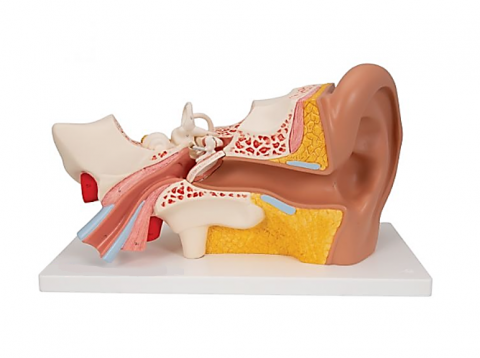

Modelul este conceput din material plastic PVC și este frumos colorat.

Acest model este conceput ca ajutor vizual pentru predarea cursurilor de anatomie umană și igienă. Este folosit pentru a demonstra structura dintelui, la studiul sistemului digestiv în gimnaziu, liceu și școli postliceale medicale.

Acest model are înălțimea de 23-26 cm, prezintă 3 rădăcini, o secțiune longitudinală prin care se poate observa structura interioara a dintelui, este conceput din material plastic PVC și este frumos colorat.